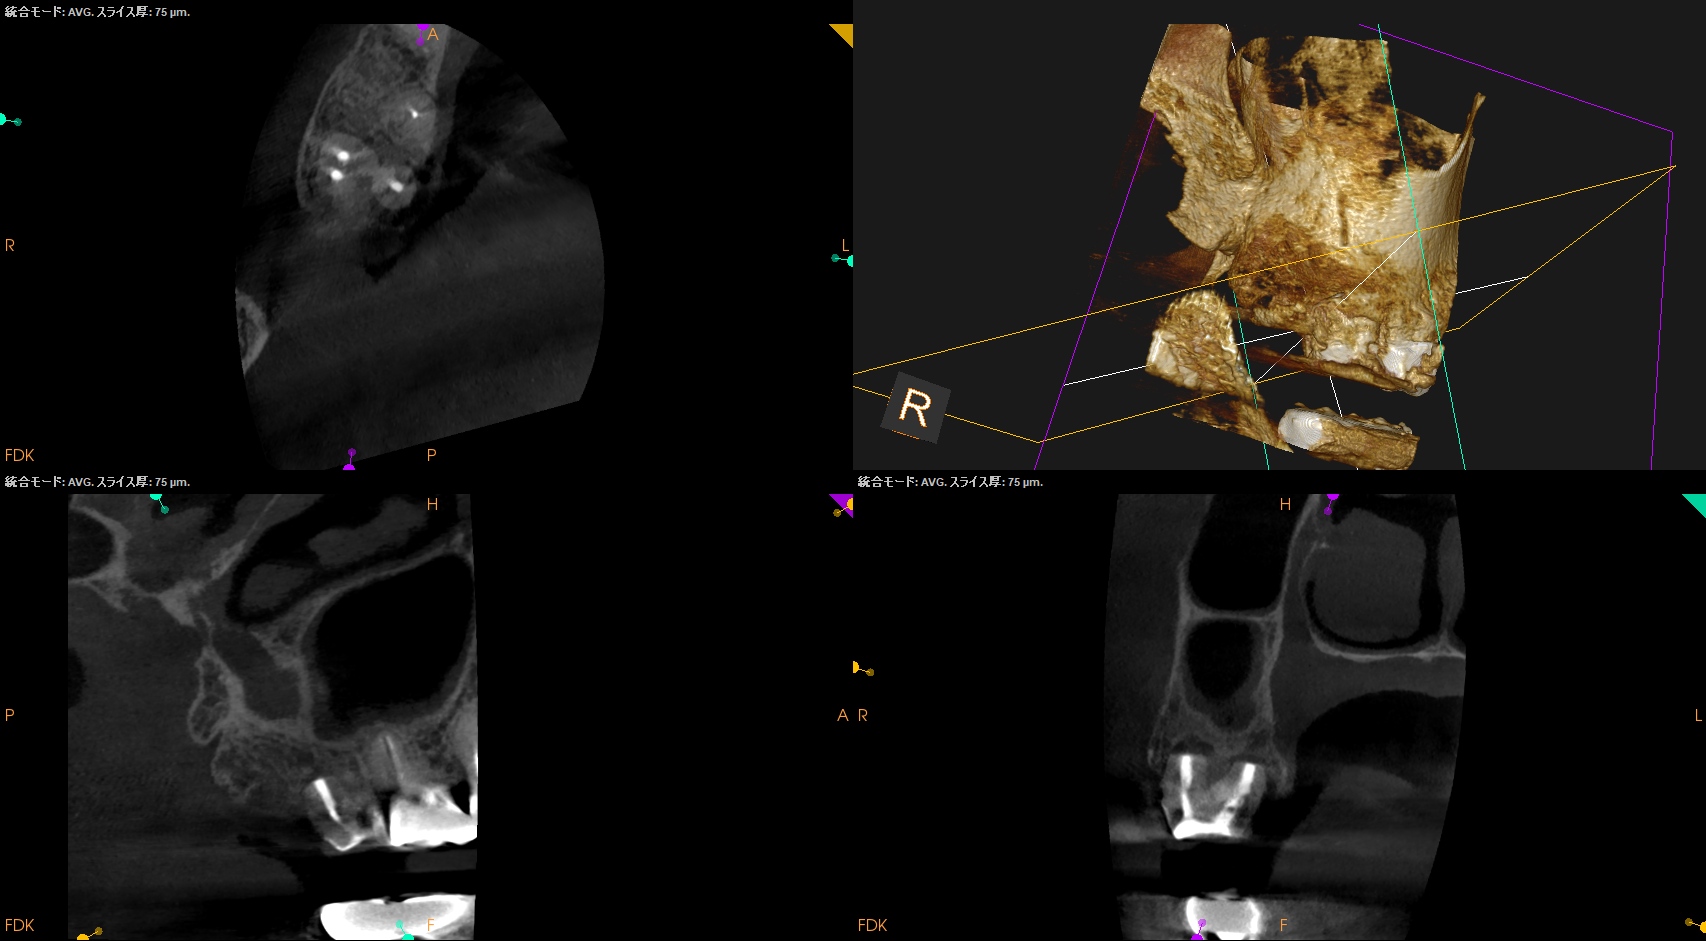

#2 Intentional Replantation 6M recall(2026.1.19)

歯牙の動揺度は生理的範囲内で歯周ポケットも深い部分がない。

術直後と比べて歯槽骨が回復し臨床症状も消失している。

最終補綴をかかりつけ医には依頼して次回は1yr recallだ。